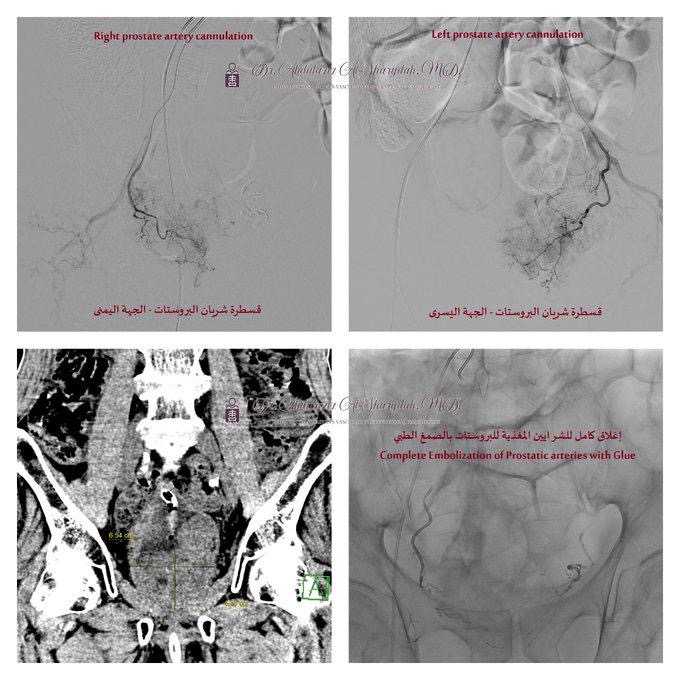

وتم إجراء قسطرة لإغلاق الشرايين المغذية للبروستاتا عبر شريان الفخذ باستخدام تقنية “الاصمام” بالصمغ الطبي تحت التخدير الموضعي، دون الحاجة إلى أي شق جراحي، وهذه التقنية المتقدمة مكنت الفريق الطبي بقيادة استشاري القسطرة والأشعة التداخلية للكبار والأطفال د. عبدالعزيز الشريدة من تحقيق نتائج فعالة وسريعة، حيث شهد المريض تحسنًا كبيرًا في اليوم التالي، وتمكن من التبول بشكل طبيعي دون أي نزيف، مما سمح بخروجه من المستشفى بعد يوم واحد بحالة صحية مستقرة.